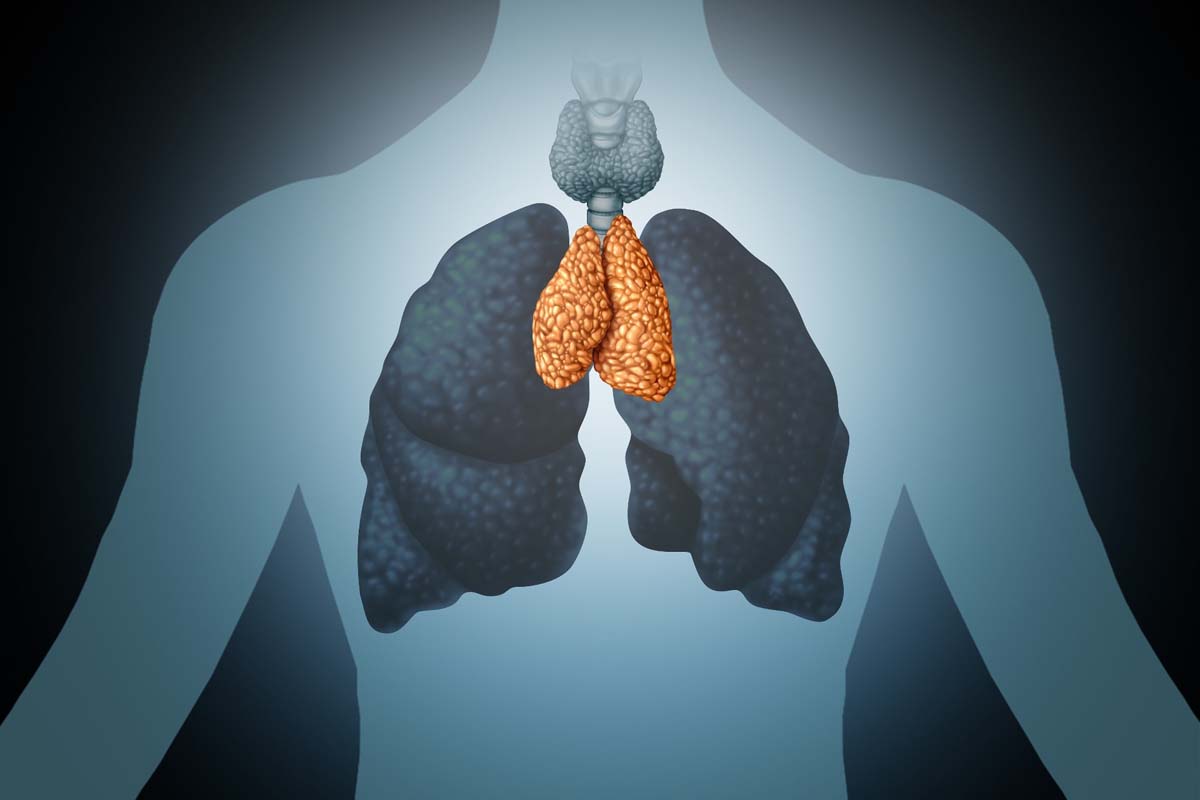

Анатомия и физиология тимуса

Тимус, или вилочковая железа, — это орган, играющий ключевую роль в развитии иммунной системы человека, особенно в детском возрасте. Расположен он в грудной клетке, непосредственно за грудиным и между легкими. В детском возрасте тимус активно функционирует, но с возрастом его активность уменьшается, и он постепенно заменяется жировой тканью.

Одной из основных функций тимуса является «обучение» T-лимфоцитов — основных клеток иммунной системы. Здесь эти клетки развиваются и «учатся» распознавать чужеродные агенты, такие как вирусы или бактерии, и бороться с ними. Таким образом, тимус является неотъемлемой частью иммунной системы и обеспечивает нашу защиту от множества инфекций.